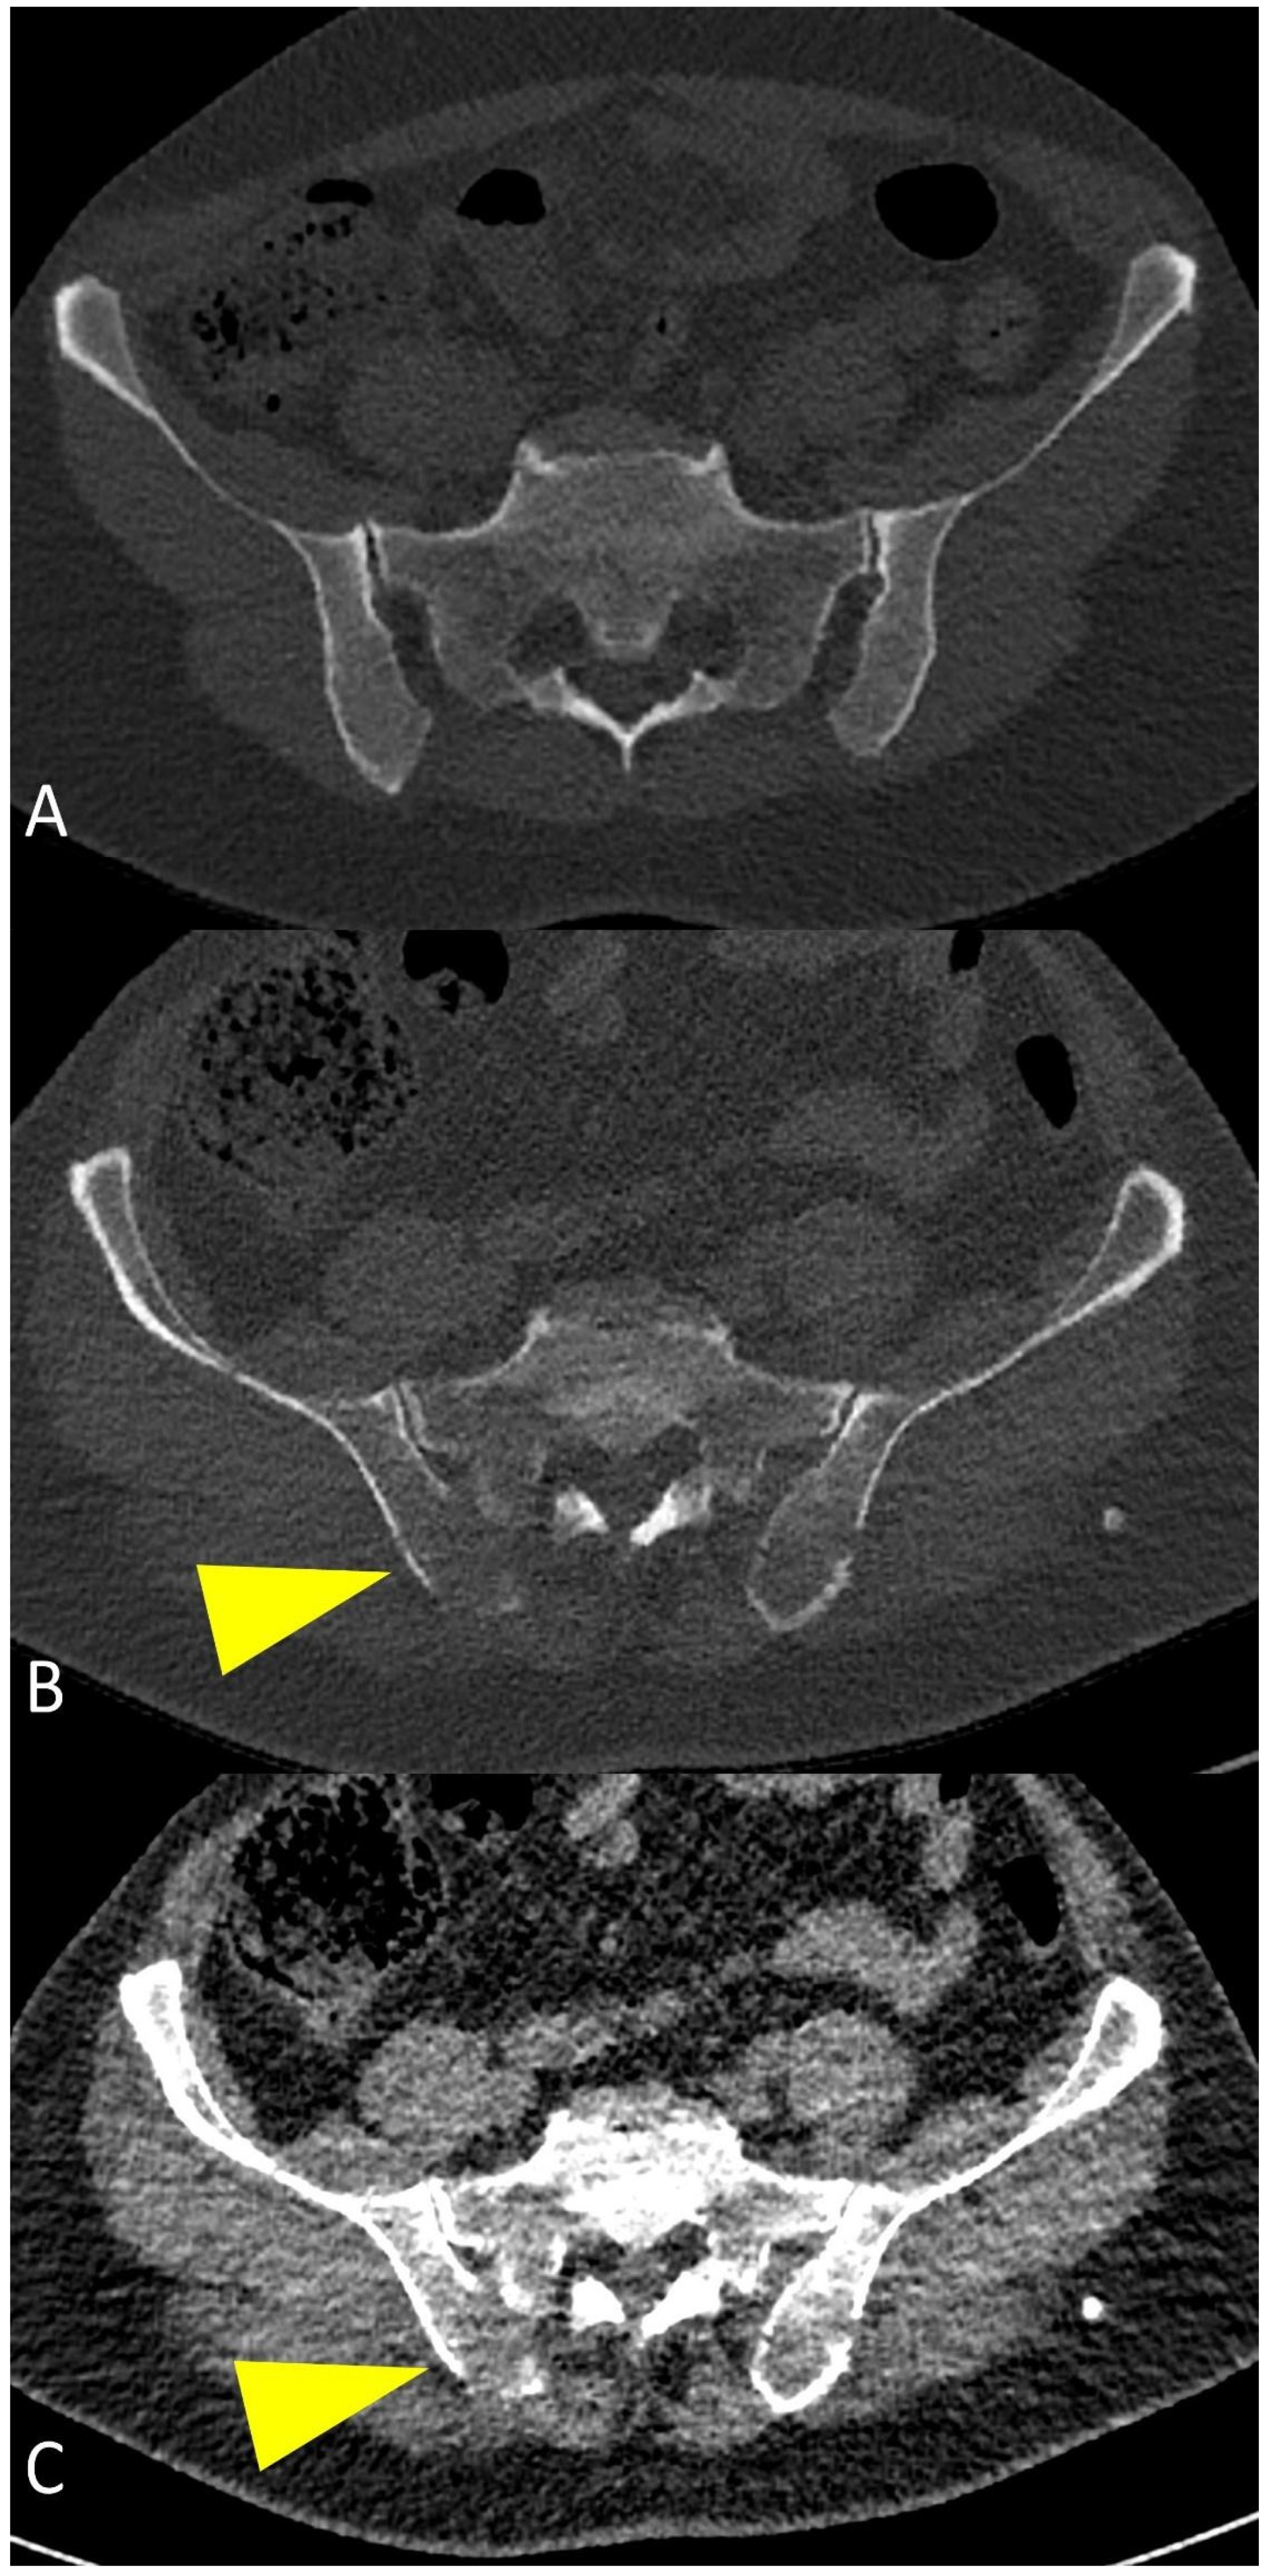

Whole-Body Low-Dose Multidetector-Row CT in Multiple Myeloma: Guidance in Performing, Observing, and Interpreting the Imaging Findings

3. WBLD-CT Imaging Findings and Evaluation